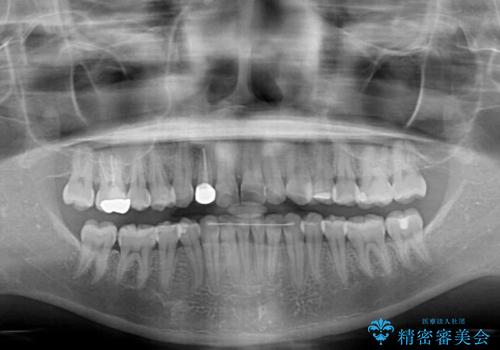

- 前歯の歯並びと不自然な色をした前歯のクラウンを気にして来院された患者様です。

上下前歯の歯列不正はインビザラインにより歯列を整え、その後に、前歯をオーダーメイドタイプのオールセラミッククラウンにて補綴治療することとしました。

前歯のデコボコを一番気にしていらっしゃいましたが、矯正治療により下顎前歯が隠れるほどのディープバイトも一緒に改善され、奥歯に負担のかかりにくい咬み合わせとなりました。